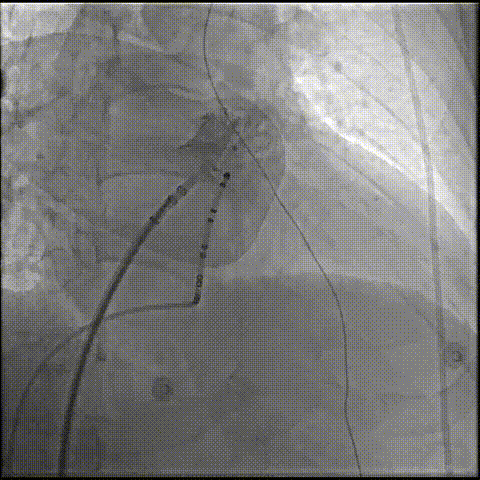

右肩位造影测量锚定区:19.44mm,开口部:30.99mm。

右肩位造影

肝位造影测量锚定区:21.62mm,开口部:29.3mm。选择LAMax LAAC® 2133 Plus型号左心耳封堵器。

肝位造影

打开封堵伞后造影评估,锚定伞锚定在主干区域,再将封堵盘打开时脱落,遂选择更换为更换为更大号的LAMax LAAC® 2436封堵器。

封堵伞打开后造影

2133封堵器封堵盘放出时脱落

2133封堵器封堵伞打开后造影

LAAC® 2436封堵器锚定伞锚定在主干区域,再将封堵盘逐渐打开,保证封堵效果,封堵盘完全打开后造影,外盘覆盖外口,封堵完全,无残余分流。

更换2436封堵器后半打开封堵伞造影